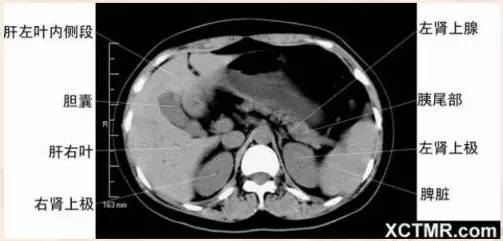

腹部CT